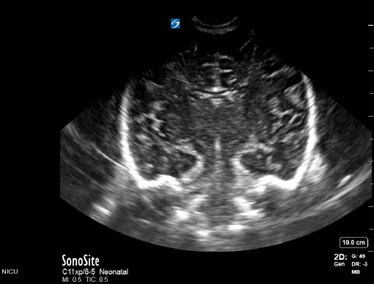

Neonatology Normal Anatomy Near Gain Too Low Image